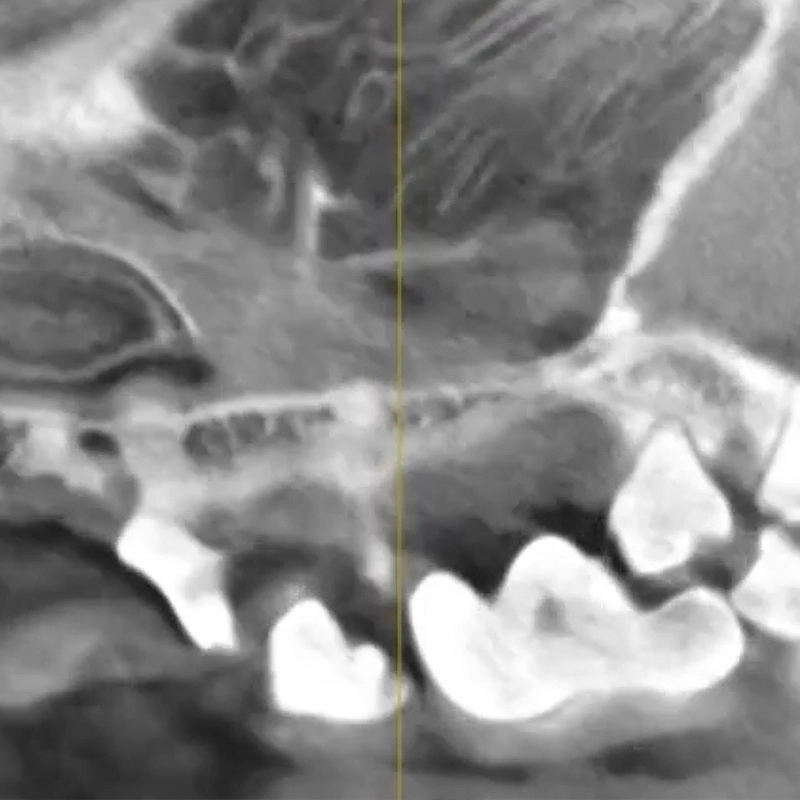

동물 전용 CT

저선량 고해상도 촬영으로 미세한 병변까지 정밀 진단합니다.

치과방사선 장비

치아 뿌리와 치조골 상태를 정확하게 파악합니다.

소형견에서 진행된 치주염을 방사선 검사로 정확히 진단한 뒤 상태에 따라 발치와 치주 처치를 진행했습니다.